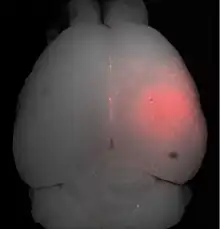

- Ultrasons focalisés avec des microbulles

Les ultrasons peuvent être focalisés sur n'importe quel domaine du cerveau. C'est ainsi que l'on peut ouvrir la barrière hémato-encéphalique sélectivement sur des régions délimitées du cerveau. Les médicaments administrés pénétreront alors sur la zone ainsi ciblée[138]. On peut suivre le ciblage des zones par une IRM simultanée : il suffit d'administrer un produit de contraste IRM, comme du gadolinium convenablement chélaté, qui pénètre dans le cerveau à travers les parties de la barrière hémato-encéphalique ouvertes. Ces parties deviennent alors visibles en IRM. Les produits de contraste ne sont pas en mesure de franchir la barrière aux endroits où elle n'est pas ouverte.

Sur le modèle animal de la souris, on a utilisé des ultrasons focalisés dans le domaine de 0,5 à 2 MHz[139], avec de brèves impulsions de l'ordre de la milliseconde, répétées à intervalles de 1 s, pour une durée totale inférieure à une minute[140]. La fréquence optimale se situe au-dessous de 1 MHz[141]. La puissance acoustique instantanée est inférieure au watt, et donc la puissance moyenne de l'ordre du mW. Les microbulles utilisées sont en général des microbulles autorisées pour l'échocardiographie de contraste. Elles ont typiquement un diamètre de 3 à 5,5 μm, et sont composées typiquement d'albumine humaine, remplie d'octafluoropropane ou de gaz lourd semblable[142].